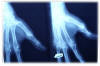

Artritis psoriásica y falange bífida.

Artritis psoriásica.